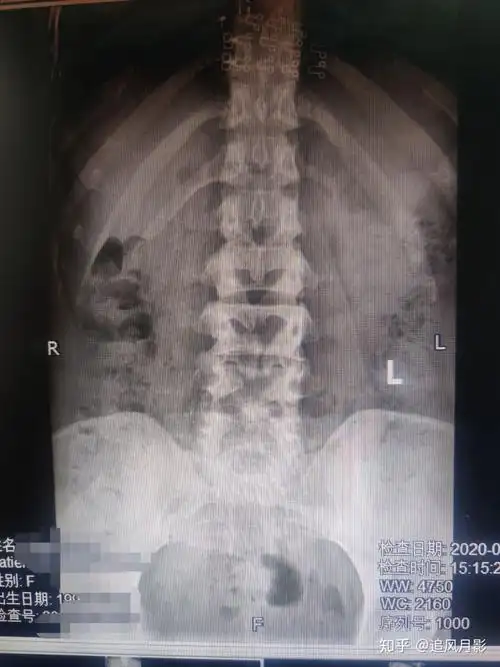

千万不要小看先天性脊柱裂!早期发现蛛丝马迹,对症治疗是关键

多节段显性脊柱裂周末门诊坑真多

隐形脊柱裂的腰骶椎隐裂生理病理表现